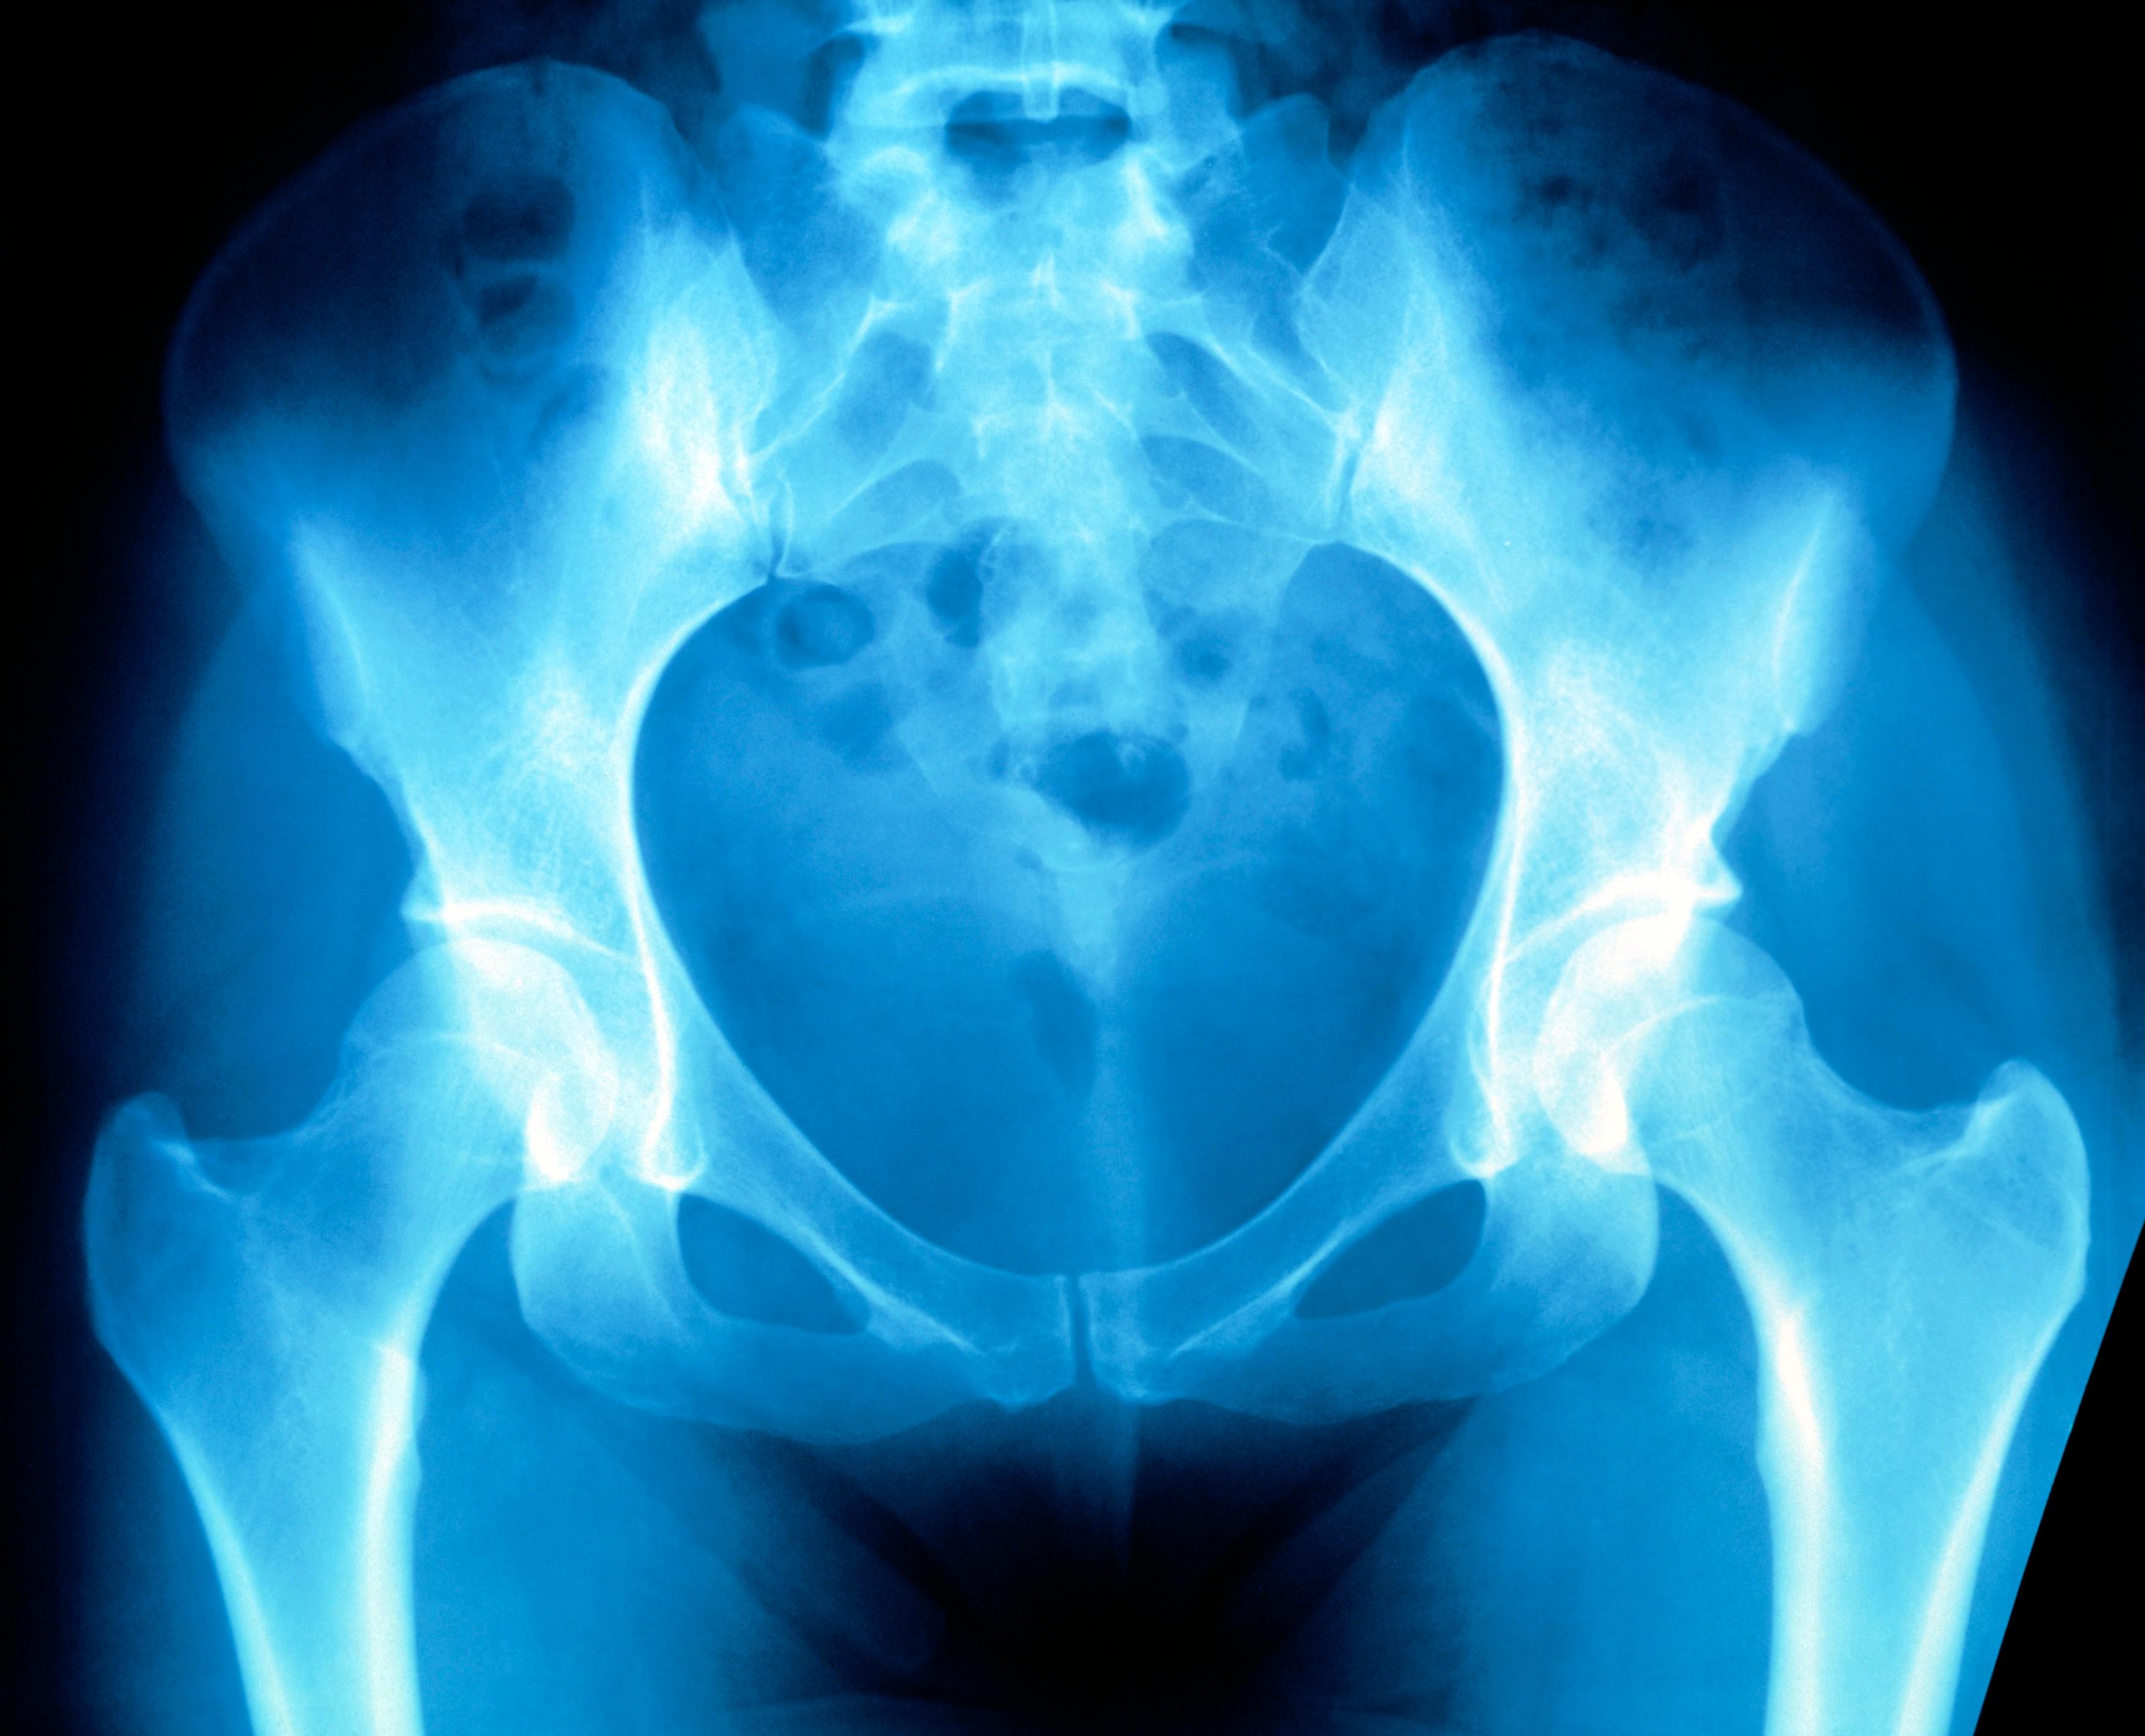

Rentgenový snímek ženské pánve | Profimedia

Osteoporóza je velmi rozšířené onemocnění. V naší republice je okolo 800 000 nemocných. Samotné onemocnění nebolí jeho následky však ano. O léčbě a prevenci v rozhlasové Radioporadně mluvil primář Ortopedického oddělení Pardubické nemocnice MUDr. Petr Hoza.